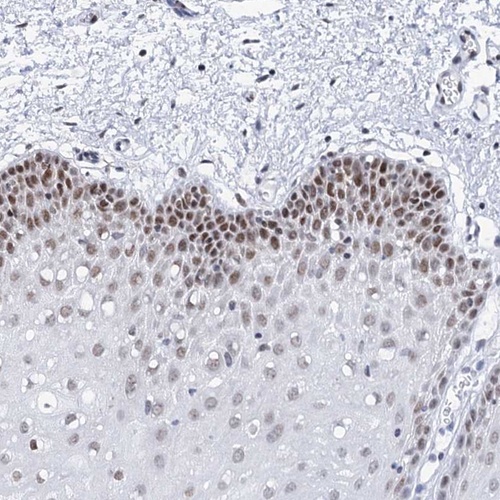

Immunohistochemical staining of human oral mucosa shows moderate nuclear positivity in squamous epithelial cells.